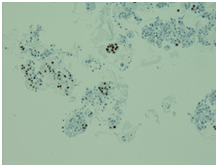

Initially, we thought about anaplastic thyroid cancer or lymphoma because of very rapid growth of thyroid mass. Thyroid ultrasound examination showed an enlarged thyroid gland; its structure was hypoechogenous and non-homogenous. Enlarged regional lymph nodes were also noted with obliteration of their ovoid morphology and loss of the echogenic hilum (Figure 1). Further imaging evaluation with contrast-enhanced computed tomography of the neck revealed an irregular tumor mass, which infiltrated neck soft tissue and vessels, causing airway stenosis up to 1 cm in diameter. The image was similar to hypo pharyngeal cancer. Also, by reason of voice changes, he was reviewed by an otolaryngologist and diagnosed a paralysis of one side vocal cord. Biochemical testing of thyroid function showed subclinical hyperthyroidism. After 1 week, thyroid ultrasound was repeated: thyroid was dramatically increased in size with its hypoechogenous and non-homogenous structure. On both lobes it was observed some up to 18 mm hyperechogenous and isoechogenous mixed nodes with pathological regional lymph nodes (Figure 2). Thyroid ultra sonography-guided fine-needle aspiration cytology (US-FNAC), cervical lymph nodes and laryngeal biopsies and particularly immunocytochemistry documented metastasis from primary lung cancer. Immunohistochemistry demonstrated that these cells were positive for TTF-1 and negative for thyroglobulin, consistent with metastatic disease from lung origin (Figure 3). The patient was deemed a nonsurgical candidate.

Figure 3 On immunocytochemistry, the malignant cells were focally positive to thyroid-transcription factor-1 (TTF-1).